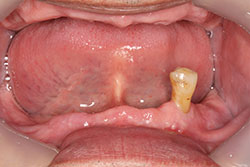

総義歯 男性総義歯 MTC 2025.09.29 治療前 治療後 治療名称咬合挙上しフルバランスドを与えることで様々な不定愁訴が改善された1症例 アイヒナー分類C2期間–費用–治療内容–治療に伴うリスク– 女性両側遊離端 MTC 前の記事 女性総義歯 Full 次の記事